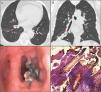

The patient was referred to a pulmonologist in 2016 with a probable diagnosis of severe asthma, and forced spirometry was repeated, showing FVC: 1.54l (61%), FEV1: 1.04l (57%), FEV1/FVC: 0.67. In view of these findings, high-resolution computed tomography (HRCT) of the chest was performed, revealing an image of calcium density in the bronchus of the right lower lobe with small distal atelectasis. Fiberoptic bronchoscopy confirmed the presence of a foreign body that could be extracted with forceps, despite significant inflammation of the adjacent bronchial mucosa. The patient was unable to remember any episode of aspiration that could be related. The pathology laboratory reported that the sample was consistent with a fragment of bony tissue (Fig. 1). After extraction, the patient's previous clinical symptoms resolved.